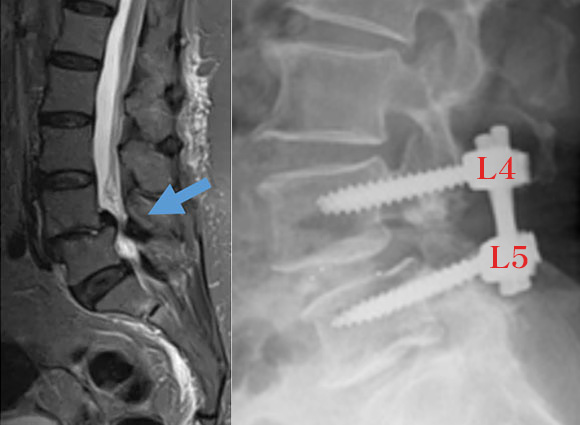

後方椎体固定術

後方椎体固定術とは

腰椎のすべり症や腰部脊柱管狭窄症の治療として行われる手術です。

すべり症は、加齢により腰椎(特にL4とL5)の関節が緩み、椎間板の高さが低下し、L4椎体が前方にずれる病気です。

これにより黄色靭帯が肥厚し、神経を圧迫して坐骨神経痛や腰痛、進行すると麻痺を引き起こします。

手術では、まず背中を縦に切開して椎弓切除術と合わせて行います。神経を減圧もしますが、もともとぐらついており更なるぐらつきを防ぐために金属固定を併用します。

L4とL5にスクリューを各2本ずつ挿入し、さらに椎間板の代わりに「ケージ」を設置して安定化し、神経の環境を改善します。手術は全身麻酔で行われ、1か所の手術時間は1.5~2時間程度です。